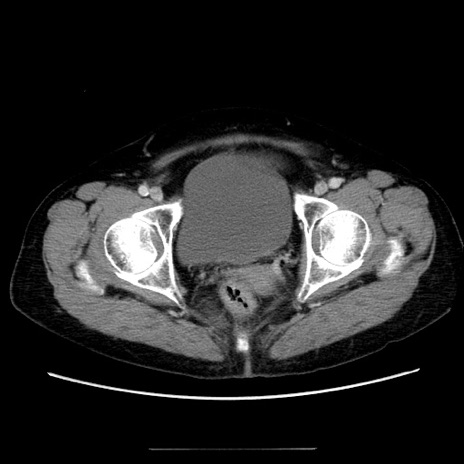

症例5(横断像)

【症例】70歳代女性

【主訴】お腹が張る

【現病歴】1週間くらい前から腹部膨満の自覚あり。昨日夜から増悪したため、本日救急外来受診。

【身体所見】意識清明、BT 36.5℃、BP 165/106mmHg、HR 80bpm、SpO2 98%、腹部:膨満、軟、自発痛・圧痛なし、触診にて不快感あり、腸蠕動音:減弱

【データ】WBC 12600、CRP 1.04